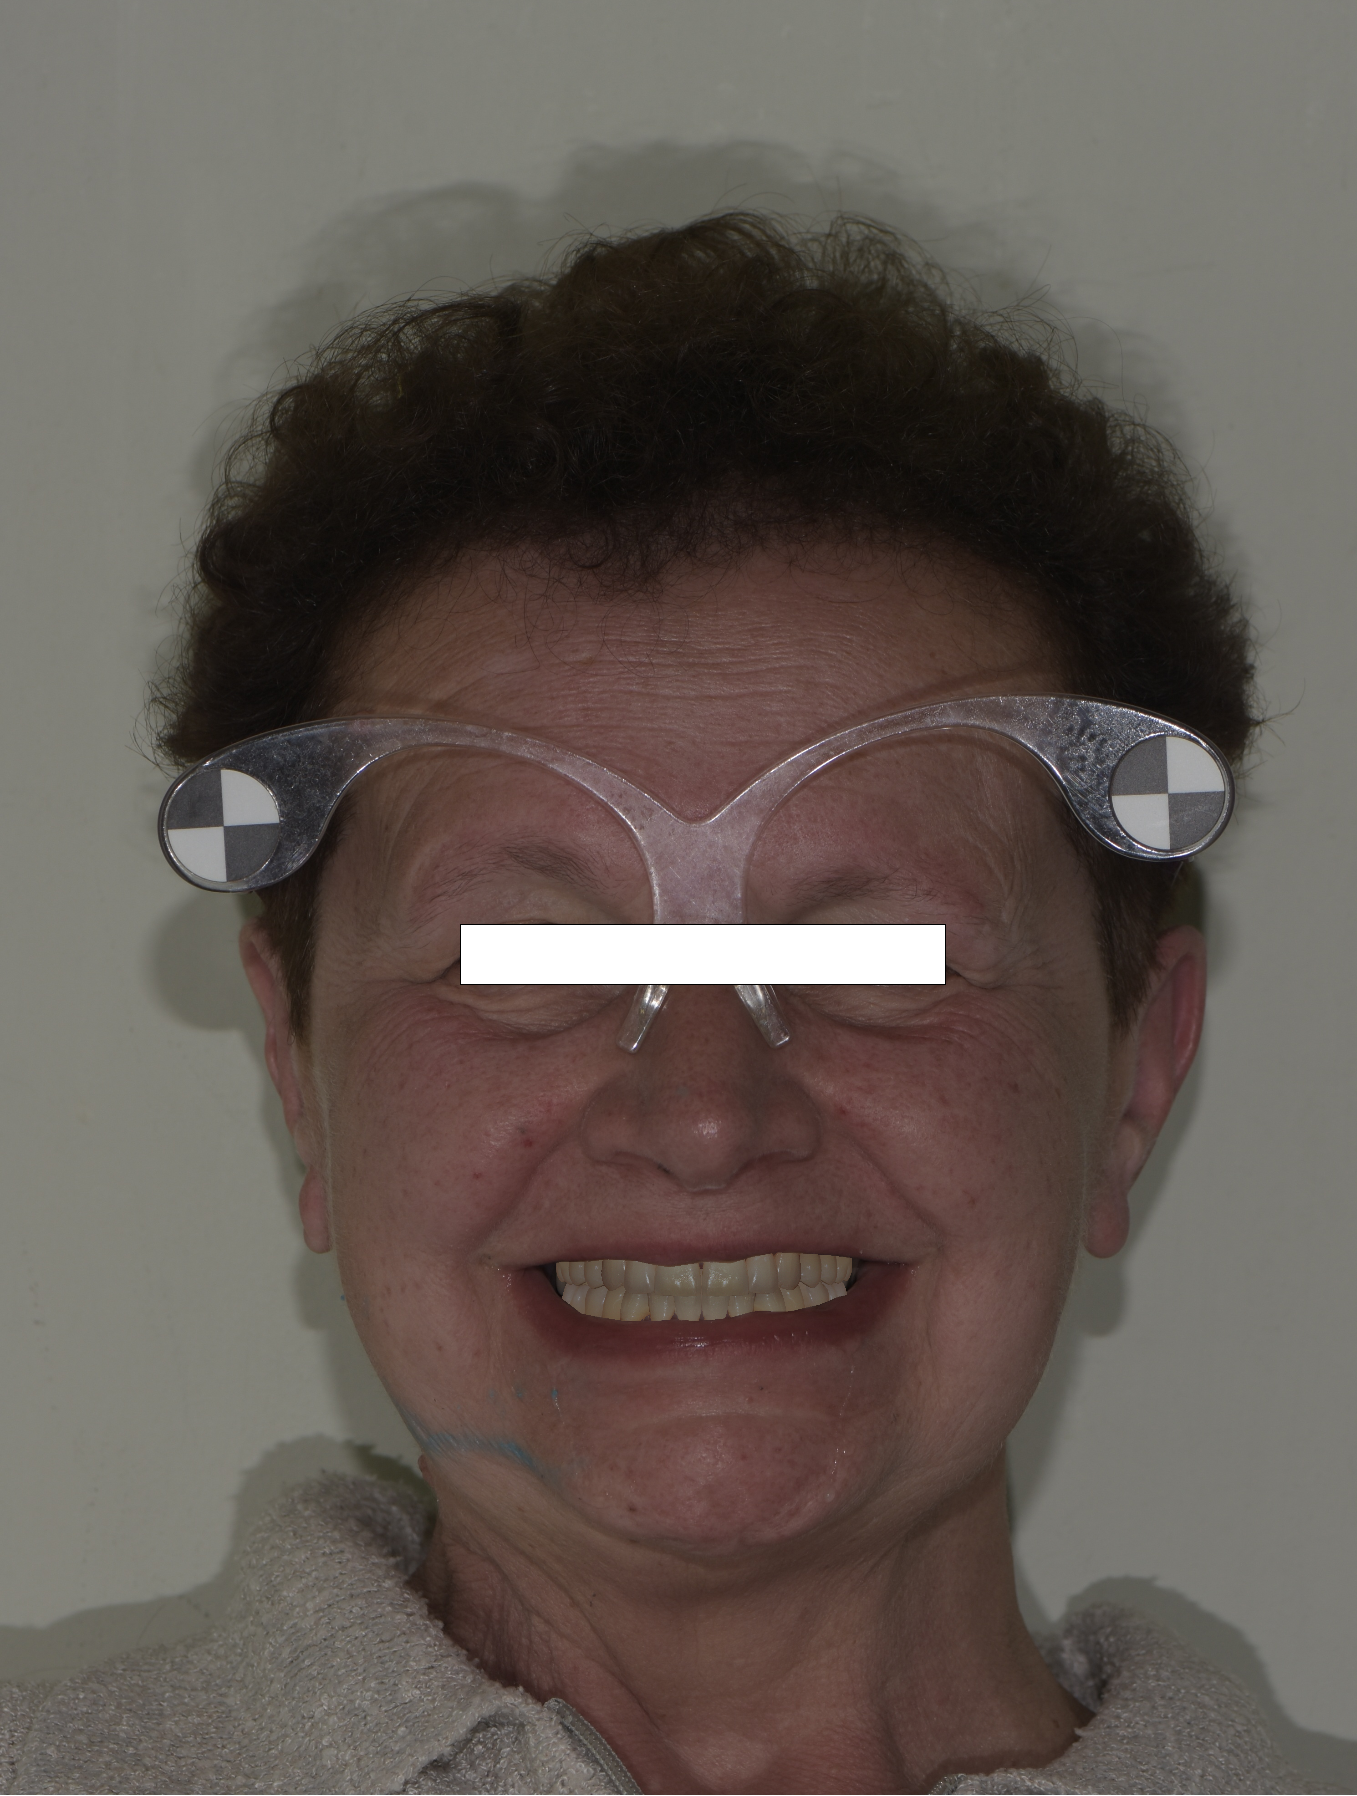

La fase protesica inizia con la ribasatura delle protesi provvisorie per rilevare la corretta anatomia della cresta. Quindi si procede a scansionare con scansione intraorale le impronte ottenute fuori dal cavo orale, poi le protesi provvisorie ribasate ricollocate nel cavo orale e la loro occlusione. Infine, si scansionano le creste edentule dopo aver posizionato gli scan body per tecnica digitale per rilevare la posizione degli impianti. Per la pianificazione sono scattate delle fotografie intraorali ed extraorali per la definizione dei limiti perimetrali del volto al fine di poter eseguire la programmazione del caso tramite il software di previsualizzazione. Le scansioni così ottenute sono poi inviate al laboratorio per la realizzazione di un prototipo delle protesi in prova.

Durante la seconda seduta della fase protesica si provvede alla prova dei prototipi in polimetilmetacrilato (PMMA) avvitati per verificare la linea del sorriso, l’occlusione, la forma

degli elementi dentari e la dimensione verticale. Sebbene già molto precisi i prototipi sono ribasati con silicone morbido per permettere al laboratorio di ottenere un accoppiamento perfetto e la massima aderenza tra mucose e protesi.